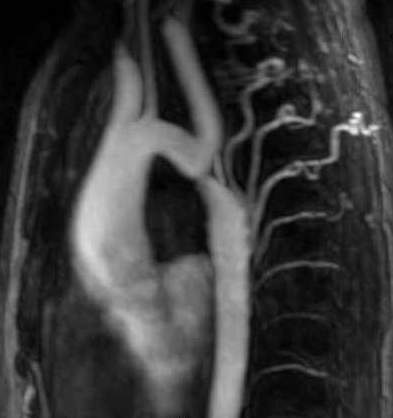

Image

Contrast enhanced MR angiography"

Fig. 22. Left sided segmental occlusion at the iliofemoral segment

CT angiography

Fig. 23. Bilateral superficial femoral artery occlusion with collateral filling

Multi-slice CT is able to perform CT angiography scans that map the body from the diaphragm to the ankles depicting the complete arterial tree with adequate intensity and with appropriate spatial resolution. In most cases this has a sufficing diagnostic value and it is especially advantageous for the rapid assessment of patients in poor condition. For the MRA of this wide region a special table toggling technique is required. This method applies prolonged injection of intravenous bolus contrast medium, and in three table-toggling steps it can visualize the arterial system of the abdominal aorta and the peripheral arteries up to the ankle with an acceptable spatial resolution. MRA examinations has the best diagnostic value for lesions presenting at the aortoiliac and femoropopliteal regions in cases with a relatively limited extension and a reasonable severity. CTA examination (with specific contrast injection protocol) provides better spatial resolution tough even in this region starting to replace angiography as a first choice of examination in the diagnostics of acute coronary syndromes.